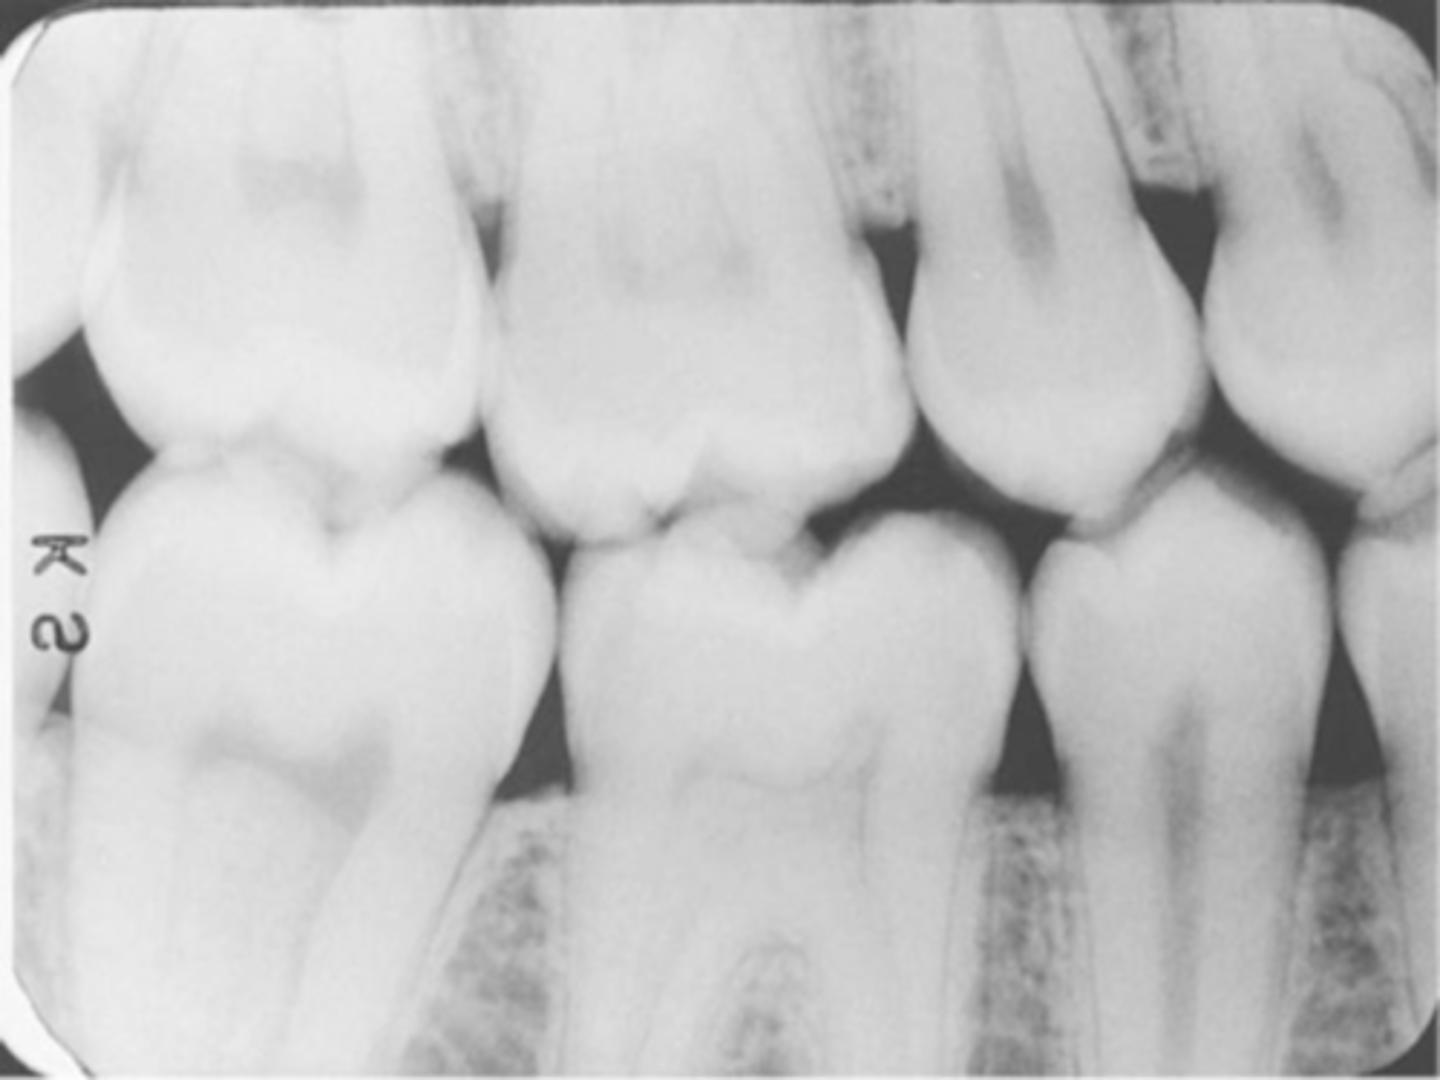

Premolar Bite-Wing

-Bite-Wing must be positioned so that the resulting image shows both max and mand premolars and the distal contact of the canines.

-Receptor must be positioned so that the front edge of the receptor is aligned with the midline of the mand. canine.

Molar Bite-Wing

-Bite-wing must be positioned so that the resluting image shows both max and mand molars, and centered over the mand 2nd molar.

-Receptor must be positioned so that the front edge of the receptor is aligned with the midline of the mand. 2nd premolar